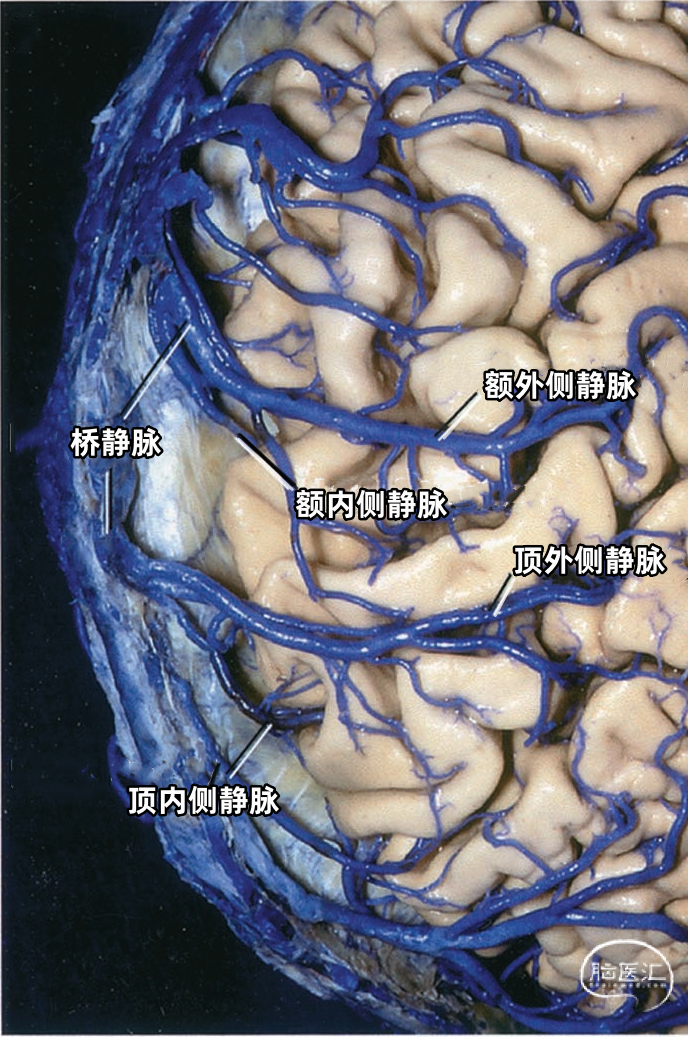

静脉腔隙(Venous lacunae),也称为静脉湖、静脉间腔、静脉间隙,来自硬脑膜的引流静脉在上矢状窦附近扩大形成静脉腔隙,它位于两层硬脑膜之间(下图)。 静脉腔隙主要接受硬脑膜内硬脑膜静脉的回流,也引流板障静脉的血液。 静脉腔隙内壁有蛛网膜颗粒(上图),进入上矢状窦的皮层静脉(上图)往往在静脉腔隙下方走行,直接汇入矢状窦,而不是直接进入静脉腔隙。大部分途经静脉腔隙下方的静脉与静脉腔隙分别开口入窦,但有些静脉与静脉腔隙有共同的入窦开口,极少数的静脉直接引流入静脉腔隙。 也有桥静脉(上图)先在窦旁潜行进入硬膜再汇入窦,硬膜内潜行使空腔扩大形成硬膜窦。静脉腔隙和硬膜窦都与矢状窦相通。 额叶后部和顶部的静脉腔隙最大和最恒定,枕部和额叶前部的静脉腔隙较小(上图)。 通常每侧都有2或3个这样的静脉腔隙,额部一个小静脉腔隙,顶部一个大的静脉腔隙,枕部一个大小介于前两者之间的静脉腔隙。 在年龄大的个体,这些腔隙趋向于融合,以致于每侧形成一个纵长的腔隙(下图)。 下图示切除大的静脉腔隙,显露下方进入上矢状窦的静脉。左侧中央静脉在中央沟上端注入上矢状窦。右侧中央静脉向前越过中央前回加入上矢状窦。

下图示切除静脉腔隙,显示上矢状窦右侧面。可见静脉在静脉腔隙下方进入上矢状窦。额内侧静脉、额外侧静脉以及顶内侧静脉、顶外侧静脉经常在入窦前汇合成共干,然后进入上矢状窦。

多数皮层静脉由单根起始,逐渐接受属支。相邻区域的皮层静脉可汇合成为一支桥静脉,穿出蛛网膜下腔,最后汇入硬膜窦。另外,引流半球内侧、外侧和底面的静脉,可能在交界区形成为一支桥静脉,最后汇入一个静脉窦。大脑内侧和外侧的上升静脉经常在半球上缘汇合,并进入上矢状窦;半球外侧下降的引流静脉和半球底面向外的引流静脉可在半球下缘汇合,进入颅底的硬膜窦。少数皮层静脉加入脑深部静脉系统。 相邻区域的血管间有互补关系,即某一静脉引流的区域增多,则相邻静脉的引流范围随之减少。在脑叶或面的主要引流静脉组之间也有类似的互补关系。

▼1.额叶

上矢状窦组(上图 深蓝色)由回流至上矢状窦的静脉组成,包括引流额叶、顶叶、枕叶内侧、外侧面上部皮层以及额叶眶面前部的静脉。 注入上矢状窦的大脑外侧面静脉包括额极静脉、额前静脉,额中静脉、额后静脉,中央前静脉、中央静脉、顶前静脉、顶后静脉、枕静脉和Trolard静脉。 注入上矢状窦的大脑内侧面静脉(上图 蓝色)包括额前内侧静脉,额中内侧静脉、额后内侧静脉、旁中央沟静脉、顶前内侧静脉、顶后内侧静脉和距状后静脉。 一般静脉在离开软膜-蛛网膜注入上矢状窦前,会在硬膜下腔有1~2cm长的游离段。这些静脉可能直接汇入上矢状窦,也可能先汇入硬膜内的硬膜窦,再进入上矢状窦。

构成蝶骨嵴组(上图 红色)的桥静脉走行于蝶骨内表面的静脉窦。包括外侧裂浅静脉的终末支(包括额外侧裂静脉、顶外侧裂静脉和颞外侧裂静脉)和少数外侧裂深静脉,引流外侧裂附近的额叶、颞叶和顶叶的静脉血流。 这些静脉一般汇入蝶顶窦或海绵窦,少数进入蝶基底窦或蝶岩窦。 右侧的外侧裂浅静脉(下图 红色)直接进入蝶顶窦或海绵窦前部,而左侧的外侧裂浅静脉更靠后并进入海绵窦外侧部。侧裂深静脉和大脑前静脉也汇入基底静脉前端。颈内动脉行经海绵窦。中颅窝底的硬脑膜窦与脑膜中动脉伴行。

切开邻近上矢状窦的硬膜时,一定要注意保护硬膜窦,它们有可能达上矢状窦外侧2.5cm处(上图),这些窦可能接受许多皮层静脉的回流。在切除这些窦深面的上矢状窦旁肿瘤时,要沿着窦的边缘剪开脑膜,并保留与皮层静脉连接的近端和与上矢状窦的连接的远端,然后将肿瘤从硬脑膜窦的下方分离而不伤及窦。 静脉腔隙位于中央前回、中央回和中央后回上部延伸的表面,对于矢状窦旁区域的手术有可能造成很大的障碍(上图)。据报道,胎儿的静脉腔隙缺如,随着年纪增大,静脉腔隙会增大。静脉腔隙的增大会伴有进入腔隙的蛛网膜颗粒的增大。 静脉腔隙可能从大脑镰附近的大脑半球内侧扩展至半球凸面3cm的范围。由于多数静脉走行在静脉腔隙下方,独自进入上矢状窦,所以术中进入或闭塞静脉腔隙未必会造成皮层浅静脉或窦的闭塞。即使是非常大的静脉腔隙也不会与上矢状窦弥散沟通,而是通过一个小的开口与矢状窦相连,故闭塞静脉间腔通常不会影响上矢状窦的通畅性。 窦旁脑膜瘤通常起自腔隙内的蛛网膜颗粒,皮层静脉通常在腔隙的下方而不是穿过进入上矢状窦,一般不需要闭塞附近的皮层静脉。需要通过显微手术技术将这些静脉从肿瘤下缘游离出来,而不是当它们暴露在肿瘤边缘时烧闭它们。